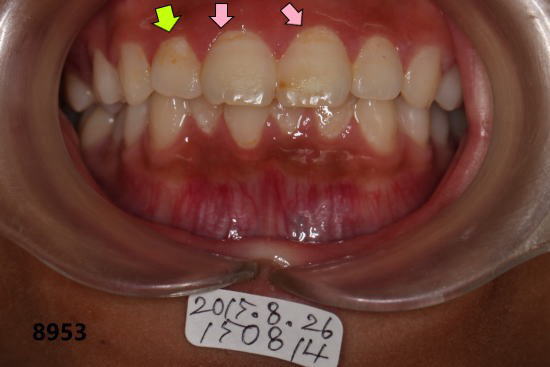

| 初診時の口腔内写真:2015年08月26日 砂糖が入ったスポーツドリンクの常用で全体の歯がむし歯になりかけ 砂糖入りのスポーツドリンクをやめて、毎日フッ素洗口をするよう勧める。 |

前歯の拡大: 矢印の所がむし歯(白濁)が進行している。 |